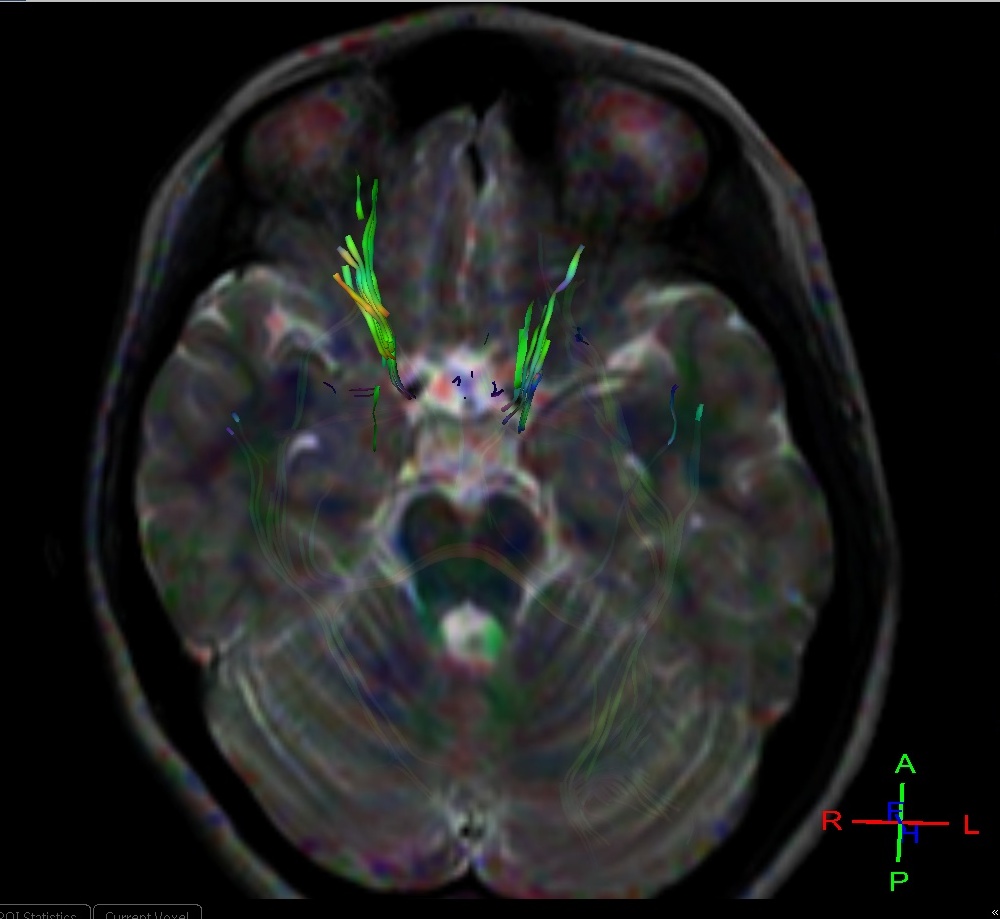

Leber's Optic AtrophyDTI Sumer's Radiology Blog

Leber's Optic AtrophyDTI Sumer's Radiology Blog Leber's Hereditary Optic Neuropathy Mri Leber hereditary optic neuropathy is a mitochondrial disorder causing acute or subacute central vision loss due to optic nerve atrophy. Leber hereditary optic neuropathy (lhon) stands as a distinctive maternally inherited mitochondrial disorder marked by. We aim to present a comprehensive review of leber hereditary optic neuropathy (lhon), detailing currently established. Leber's hereditary optic neuropathy (lhon) is a maternally inherited. Leber's Hereditary Optic Neuropathy Mri.

Leber's Optic AtrophyDTI Sumer's Radiology Blog Leber's Hereditary Optic Neuropathy Mri We aim to present a comprehensive review of leber hereditary optic neuropathy (lhon), detailing currently established. Leber’s hereditary optic neuropathy (lhon) is a fairly prevalent mitochondrial disorder (1:50,000) arising from the dysfunction of the. The primary aim was to define mri features of lms and lhon, and to assess the proportions of individuals displaying features. Leber hereditary optic neuropathy is. Leber's Hereditary Optic Neuropathy Mri.